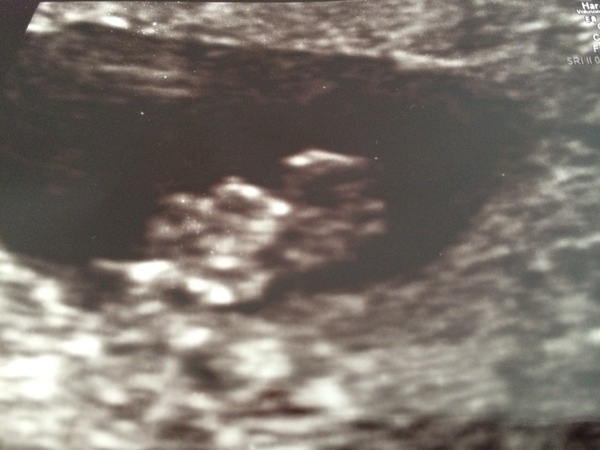

Had my early scan today, measuring 8 weeks which is just one day out of what I thought.

Everything's fine though, heartbeat and sac etc. The lady did notice a bit of blood in my womb so she said if I get some bleeding not to worry, I haven't had any up until now so we will see.

Was a struggle to get to the clinic as I feel really sick lately, but thought I would give it my best shot.

Lovely pic Siarie, I'm so jealous, I'd love to have a scan already.